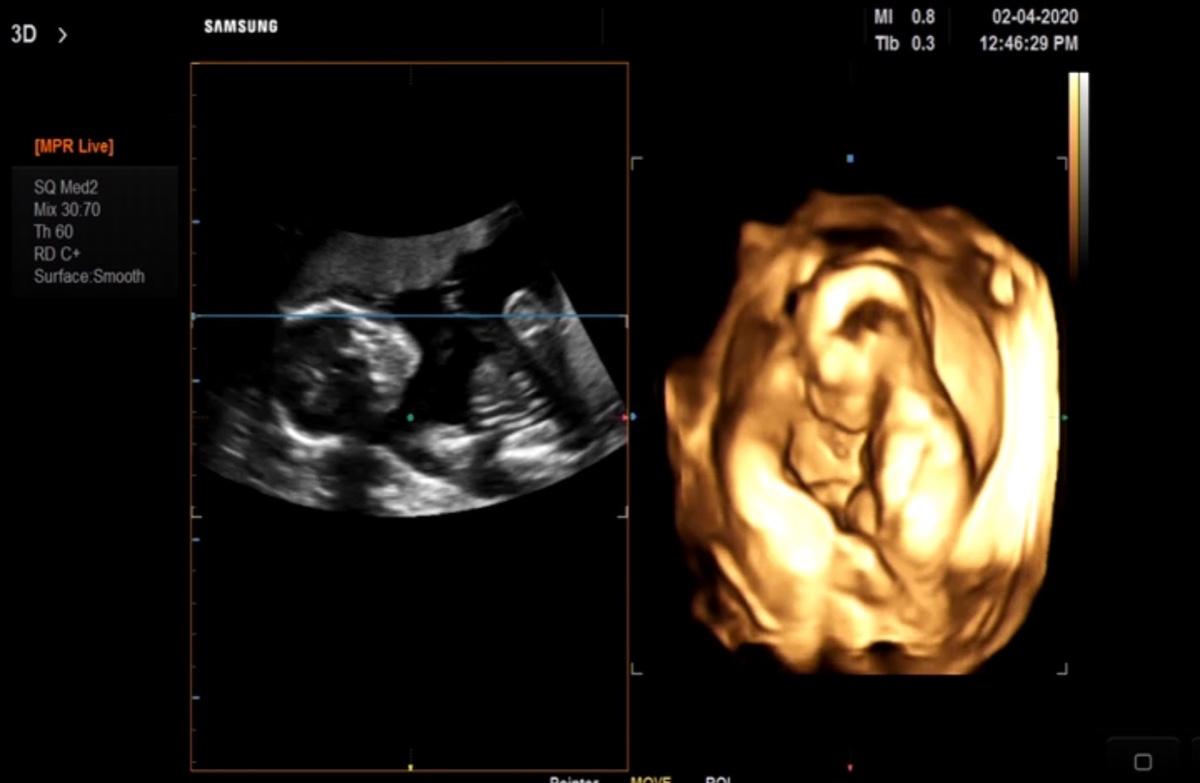

2020/02/04。臨時決定去產檢!

2月份的產檢日其實是2/22才對~

只是在2/1那天,我去做了羊膜穿刺後~

有點點出血,有點擔心,因此2/4我自己跑去給醫生看診~

還好⋯醫生照了超音波、也內診過了!

確定寶貝沒問題了!我才放心~